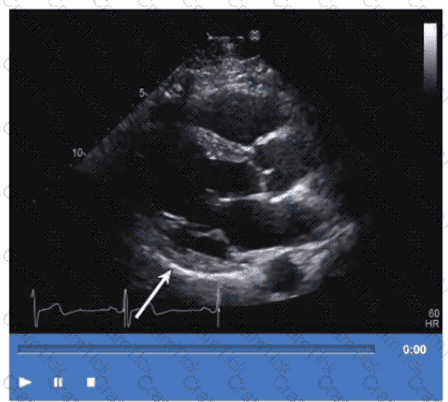

Which step is next in further evaluation of the abnormality shown in this video?

Which is the most likely abnormality represented in these images from a 48-year-old man with shortness of breath?